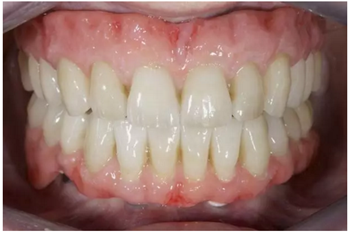

試戴上頜NobelProcera CAD/CAM海德式桿卡(IBO)以及下頜NobelProcera二氧化鋯種植橋(PIB)。

手術(shù)后16周最終修復(fù):上頜覆蓋義齒是卡扣在鈦桿卡(IBO)上,義齒牙冠部分是由二矽酸鋰玻璃陶瓷制作的單冠。下頜的氧化鋯種植長橋(PIB)上同樣也制作二矽酸鋰玻璃陶瓷的單冠并進(jìn)行粘接。